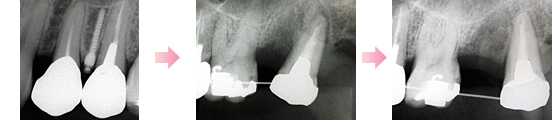

このままの状態では保存が難しい、または無理に治療しても予後に影響のでるような歯があります。

現在の詳しい状態をレントゲンやスライドお写真にて説明して、了解が得られた場合以下のような治療を行う場合があります。